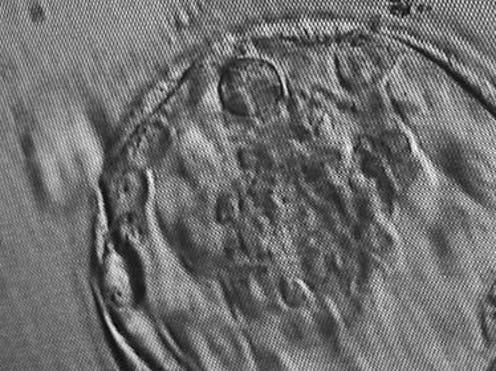

The researchers then grew these cells in 3D clusters for six days, after which some of them formed structures very similar to “blastocysts” — the final stage of embryonic development before implantation. These lab-grown structures are dubbed “iBlastoids”.

Growth process for human blastocysts (top) and iBlastoids grown in the lab from human skin cells (bottom). Monash Biomedicine Discovery Institute

The second group cultured human pluripotent stem cell lines - both embryonic stem cell lines and those created through reprogramming - in a slightly different two-step process to encourage 3D clusters to form. They called their structures “blastoids”.

While iBlastoids and blastoids both seem to be structurally and functionally similar to real blastocysts, it is not yet clear exactly how closely they resemble true embryos formed by a sperm and an egg. While the models were shown to share gene patterns and respond in culture in ways characteristic of actual embryos, researchers also saw significant anomalies, such as unsynchronised growth and cells that are not usually present in an embryo.